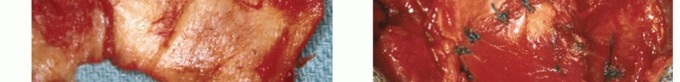

2. ## Freeze-dried Cadaver Rotator Cuff Graft

If the residual defect is too large for a biceps graft to cover, a larger graft is needed. The best choice is a freeze-dried graft of human rotator cuff. As with every graft, the musculotendinous motor (ie, the native rotator cuff) must be a functional unit, as noted earlier.

After the described mobilization techniques have reduced the size of the defect as much as possible, the graft is reconstituted in sterile saline for 30 minutes so that it becomes soft and pliable (

TECH FIG 6A

).

TECH FIG 6 • A. Reconstituted freeze-dried cadaver rotator cuff graft. B. Reconstituted freeze-dried cadaver rotator cuff graft sutures in place. (A: From Neviaser JS, Neviaser RJ, Neviaser TJ. The repair of chronic massive ruptures of the rotator cuff by use of a freeze-dried rotator cuff. J Bone Joint Surg Am 1978;60A:681-684; B: From Neviaser R, Neviaser AS. Open repair of massive rotator cuff tears: tissue mobilization techniques. In: Zuckerman J, ed. Advanced Reconstruction: Shoulder. Chicago: American Academy of Orthopaedic Surgery, 2007:177-184.)

It is then trimmed and contoured to accommodate the free edge of the native cuff and then sutured to it with nonabsorbable no. 1 sutures.

It is also trimmed to reach a trough in the anatomic neck adjacent to the greater tuberosity and secured in the same fashion as the direct repair through drill holes in the bone or by anchors, as previously described (

TECH FIG 6B